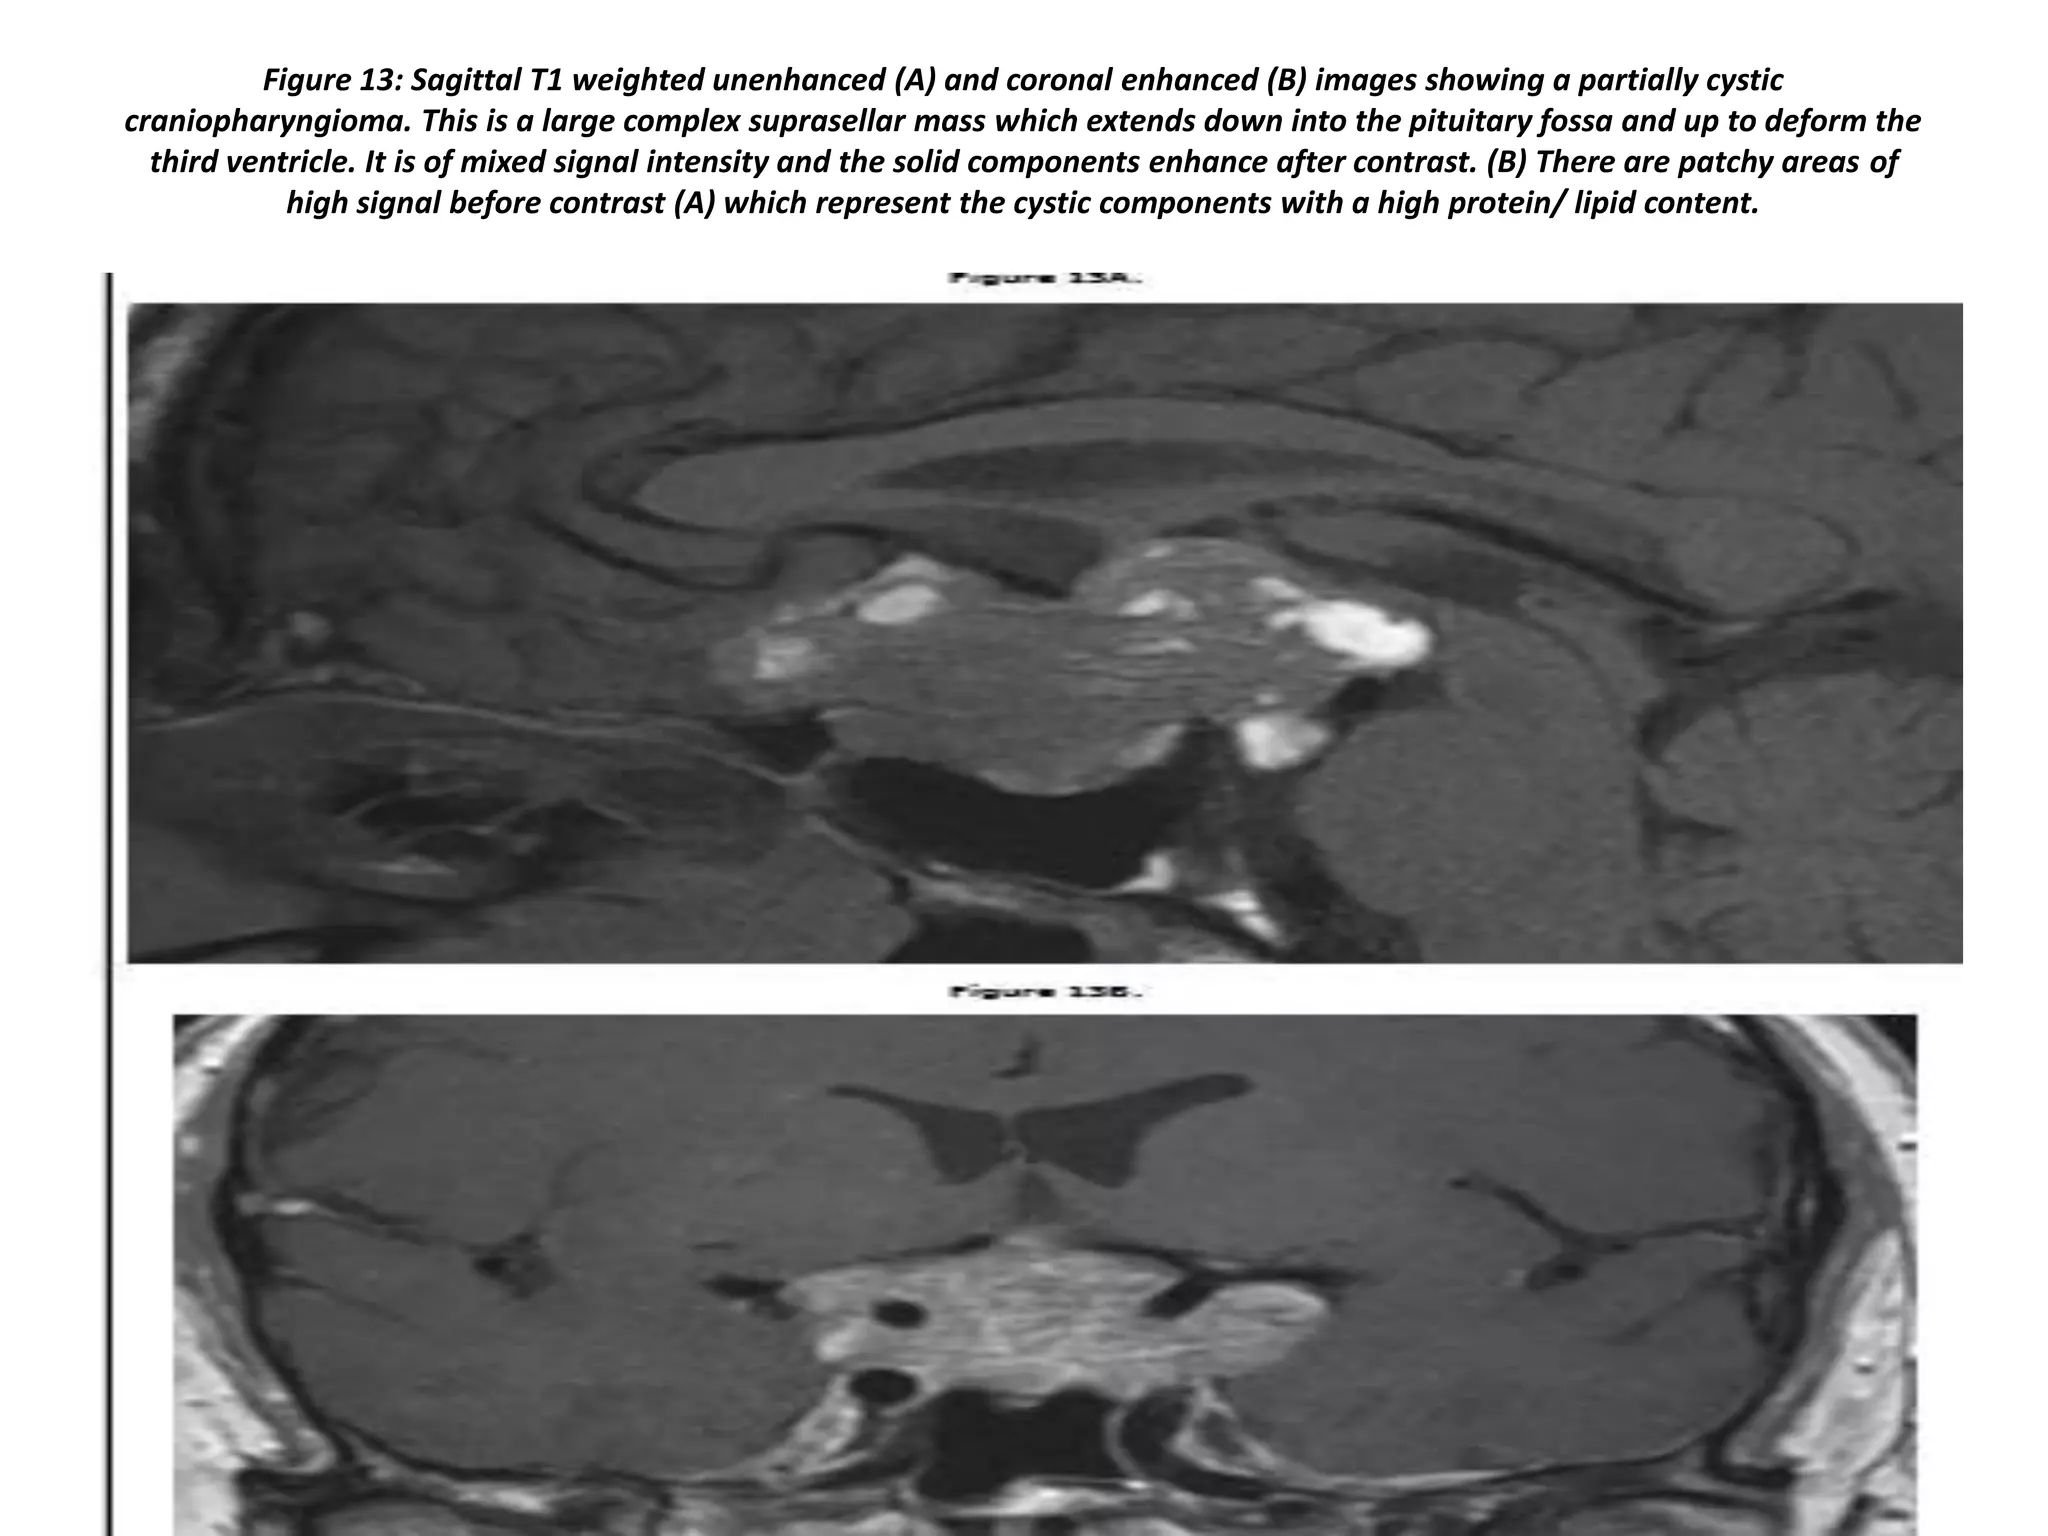

Figure 13: Sagittal T1 weighted unenhanced (A) and coronal enhanced (B) images showing a partially cystic

craniopharyngioma. This is a large complex suprasellar mass which extends down into the pituitary fossa and up to deform the

third ventricle. It is of mixed signal intensity and the solid components enhance after contrast. (B) There are patchy areas of

high signal before contrast (A) which represent the cystic components with a high protein/ lipid content.